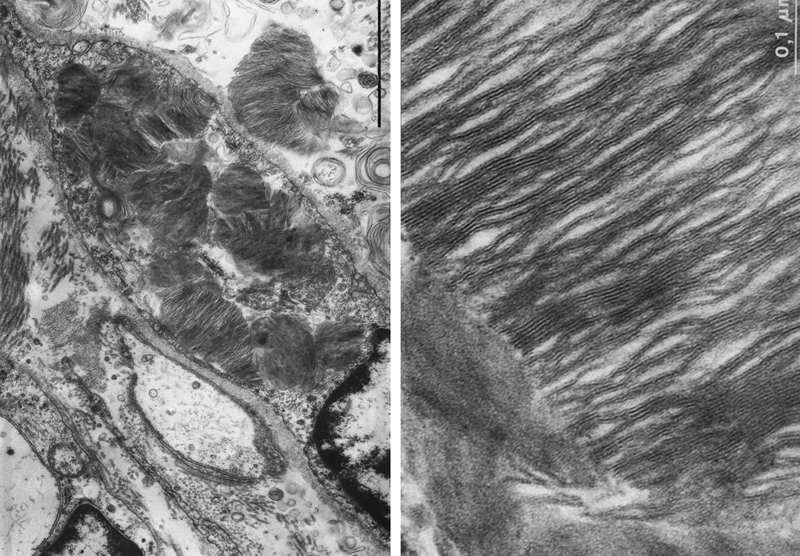

The patient was expected to die within a few days. I called Maria Mázló, the head of the Electron Microscope Laboratory, of the National Institute of Psychiatry and Neurology in Budapest. She said, the investigation would be carried out, but asked us to send fresh samples to the laboratory. I discussed the immediate autopsy with the head physician of our Pathological Department. The patient died at one o'clock at night. After the obligatory two-hour wait we were standing in the autopsy room, and the autopsy was done at three o'clock. This was the first autopsy in Hungary by a patient who died of Fabry disease, no previous reports were found. And we believe it was also the first autopsy at night in our country.

Fig. 14. Electron microscopic image of the stored material of our patient with Fabry’s disease